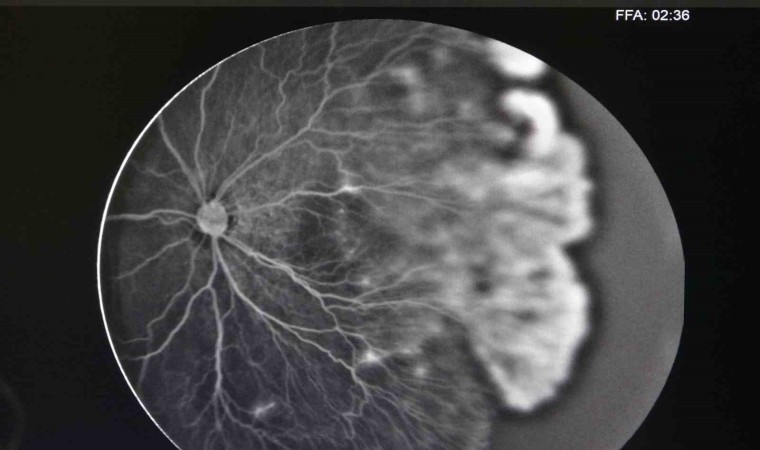

ROP tedavisi olan bebeklerde özellikle gözde retina damar gelişiminin çok önemli bir husus olduğunu değinen Ekinci, “Çünkü birçok bebekte damar gelişimi zayıf kalıp tekrar hastalığın nüksüne sebep olabilmekte. Bunu tespit edebilmek için son yıllarda tüm dünyada ve ülkemizde bazı merkezlerde göz anjiyografisi kullanılmakta. Anjiyografiyi biz genel anestezi altında uygulamaktayız. Damardan boyalı bir madde vererek gözün arkasındaki damarların gelişimini tespit etmekteyiz. Anjiyo sonucuna göre tedavi kararımızı veriyoruz. Bebekte eğer damar gelişimi eksikse veya damarlarda bizim gözümüzle göremediğimiz sızıntılar varsa lazer tedavisiyle bebeğin gözünü emniyete almış oluyoruz” diye konuştu.

Daha önce Diyarbakır’da bu sorunu tespit ettikleri bebekleri İstanbul ya da Ankara’ya sevk etmek durumunda kaldıklarını, şimdi ise cihazın olmasıyla hastaları il dışına göndermeye gerek duymadan tedavi ettiklerini ifade eden Ekinci, “Son birkaç aydır artık bizim merkezimizde de cihaz var. Bebeklerimizi il dışına göndermeden görüntülerini çekip tedavilerini yapabilmekteyiz. Anjiyo cihazının bir diğer güzel yanı sadece ROP değil, diğer retina hastalıklarında da kullanabiliyoruz” ifadelerine yer verdi.